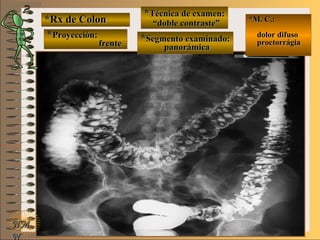

*Rx de Estómago*Rx de Estómago

**Proyección:Proyección:

**Técnica de examen:Técnica de examen:

A-A-

B-B-

C-C-